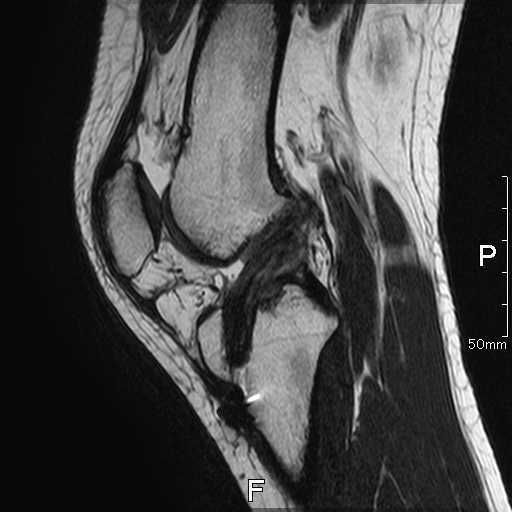

術前画像

| レントゲン | MRI |

| 骨傷なし、関節変形なし | ACLの連続性や緊張がみられない |